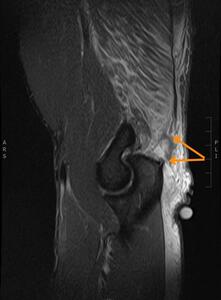

Immediate post-injury MSK US demonstrated a selective area of complete fiber non-visualization of the distal triceps tendon’s superficial portion near its insertion on the proximal ulna, indicating a high-grade partial tendon avulsion (Figure 3). The subject was referred by the physical therapist for MRI two days later. MRI findings confirmed a partial triceps tendon avulsion with a partially retracted conjoined tendon of the long and lateral heads of the triceps and tendinosis (Figure 4).